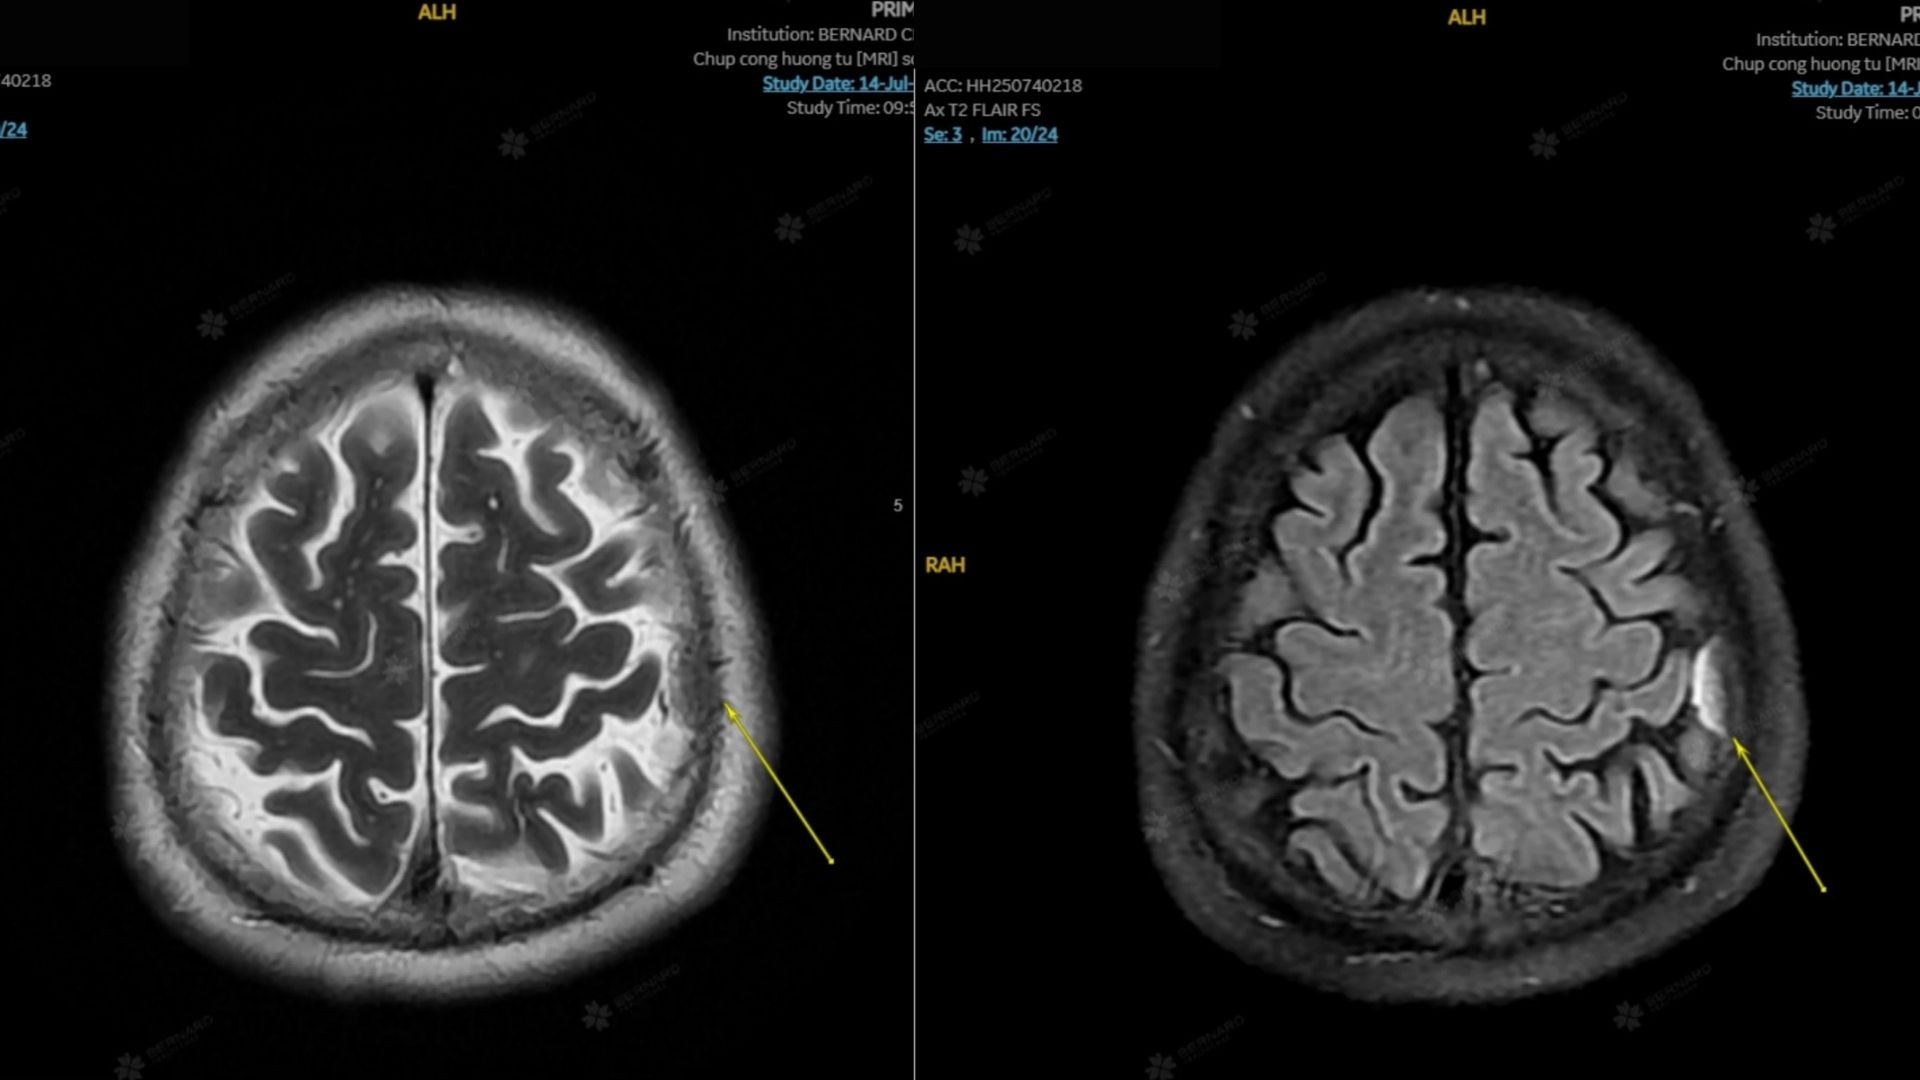

Bất ngờ, kết quả MRI ghi nhận cấu trúc dạng choán chỗ ngoài trục đỉnh trái, kích thước khoảng 10 x 20 x 16 mm, gợi ý u màng não nhỏ.

Theo đánh giá của bác sĩ tại Bernard, khối u hiện có kích thước nhỏ, nhiều khả năng là u lành tính, chưa gây chèn ép mô não và chưa tạo ra triệu chứng ảnh hưởng đến sức khỏe. Vì vậy, người bệnh chưa cần can thiệp phẫu thuật ngay, có thể trì hoãn và theo dõi.